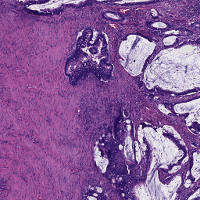

The definition of classes in our RC data is slightly different from the one coming with the CRC dataset. Therefore, we grouped corresponding classes as described in Table 2, which resulted in a 6-class problem, used to evaluate the performance of the trained ConvNet applied to CRC data. Applying the ConvNet directly to CRC data gave a poor accuracy value of 50.96% (experiment A). Based on this result, we investigated the role of staining in this classification task. For this purpose, we selected a representative RC image from the RC cohort as the template image to define the mapping parameters for the SN1 and SN2 algorithms999The function for SN1 is available in the form of look-up table at https://github.com/francescociompi/stain-normalization-isbi-2017. Successively, we stain-normalized patches in the CRC dataset and classified it again with the same ConvNet. Stain normalization allowed to remarkably improve the accuracy by more than 20%, reaching values of 75.55% (experiment B) and 73.99% accuracy for SN1 and SN2 respectively. Besides the difference in accuracy, we found that SN2 failed to normalize 3 patches of adipose tissue, and it tends to force color normalization regardless of the type of tissue considered. As an example, in Figure 4, two CRC patches are depicted, containing tumor and blood cells respectively. While both SN1 and SN2 correctly normalize stain for the tumor patch, the characteristic red color of blood cells is completely lost using SN2, while SN1 keeps a substantial component of the red channel.

Based on the positive result of the previous experiment, the question remains whether stain normalization should only be applied to test data or also to training data. To address this question, we introduced SN1 in our training and testing pipeline and evaluated the accuracy of a ConvNet trained on RC data and applied to CRC data in four different configurations, namely with (experiment C) and without (experiment D) stain normalization applied to RC (training) data and to CRC (test) data. The results are reported in Table 3, where for the sake of clarity a letter is assigned to the result of each combination. As expected, experiment D resulted in the lowest performance, since the ConvNet does not learn any stain variability from the training set, while such a variability is expected in the test set. Although all the training cases come from the same cohort and staining was done in the same lab, experiment C gave an improvement of 5% accuracy compared to B, which indicates that the ConvNet can benefit from the variability in the training set. It is worth noting that experimental settings of A represents what is commonly done in digital pathology research, where training data from a given cohort, with some variability are used to train a classifier, whose performance are evaluated on an independent set of data coming from different laboratories and stained with different procedures. Experiment B reduced the variability in the test set by adapting data to match the stain distribution of the template image. Finally, experiment C showed a substantial improvement compared to all other possible combinations of settings. Qualitative results of images in CRCt classified under the settings of experiment C are depicted in Figure 5.